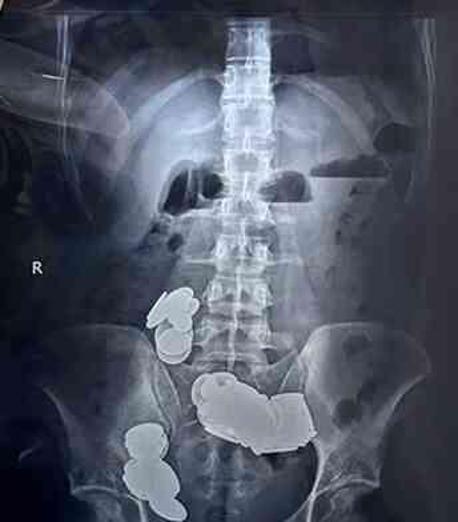

Hindistan'ın başkenti Yeni Delhi'de psikolojik tedavi gördüğü belirtilen 26 yaşındaki halterci, şiddetli karın ağrısı şikayetiyle hastaneye gitti. Haltercinin çekilen mide röntgeninde, vücut yaptığına inandığı için yuttuğu 39 madeni para ve 37 mıknatıs tespit edildi. Yeni Delhi'deki bir hastanede saatler süren ameliyat sonrası doktorlar madeni para ve mıknatısları çıkarmayı başardı.

Cerrahlar, mıknatısların ve paraların küçük bağırsakta iki ayrı döngü oluşturacak şekilde bir araya geldiğini, manyetik kuvvetin onları kilitleyerek bağırsak duvarında erozyona neden olduğunu belirtti. Madeni para ve mıknatıs yutan hasta ise, ameliyat sonrası hastanede yedi gün geçirdikten sonra taburcu edildi.